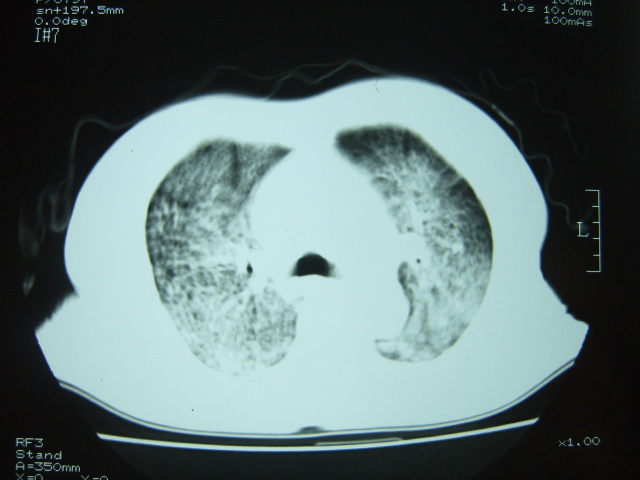

女 79岁,今日高烧,无咳嗽及痰,是否粟粒结核还是?

双肺弥漫性病变,以肺间质改变为主,

1特发性肺间质纤维化2结节病3过敏性肺炎4淋巴管播散癌.需结合临床.

胸内小结节部分融合成片,边缘模糊,

考虑肺部特殊感染-霉菌?建议痰培养。

双肺弥漫小结节状高密度,部分融合,边界不清(因为不是hrct,可能为部分容积效应引起),肺门纵隔内未见肿大淋巴结影。无胸腔积液。

考虑:急性血型播散型肺结核,不除外过敏性肺炎;建议治疗后复查。

双肺弥漫性结节影,双肺上叶为著.纵隔内可见一肿大淋巴结影,密度较高.支持急性血行播散型肺结核.双侧少量胸腔积液.

双肺弥漫基本均匀分布的小结节状高密度影,部分融合。支持急性血性播散性肺结核。

两肺弥漫分布小结节状高密度影,其大小,密度一致,分布均匀,并可见与后胸壁平行的弧状影

诊断:两肺急性血型播散形肺结核